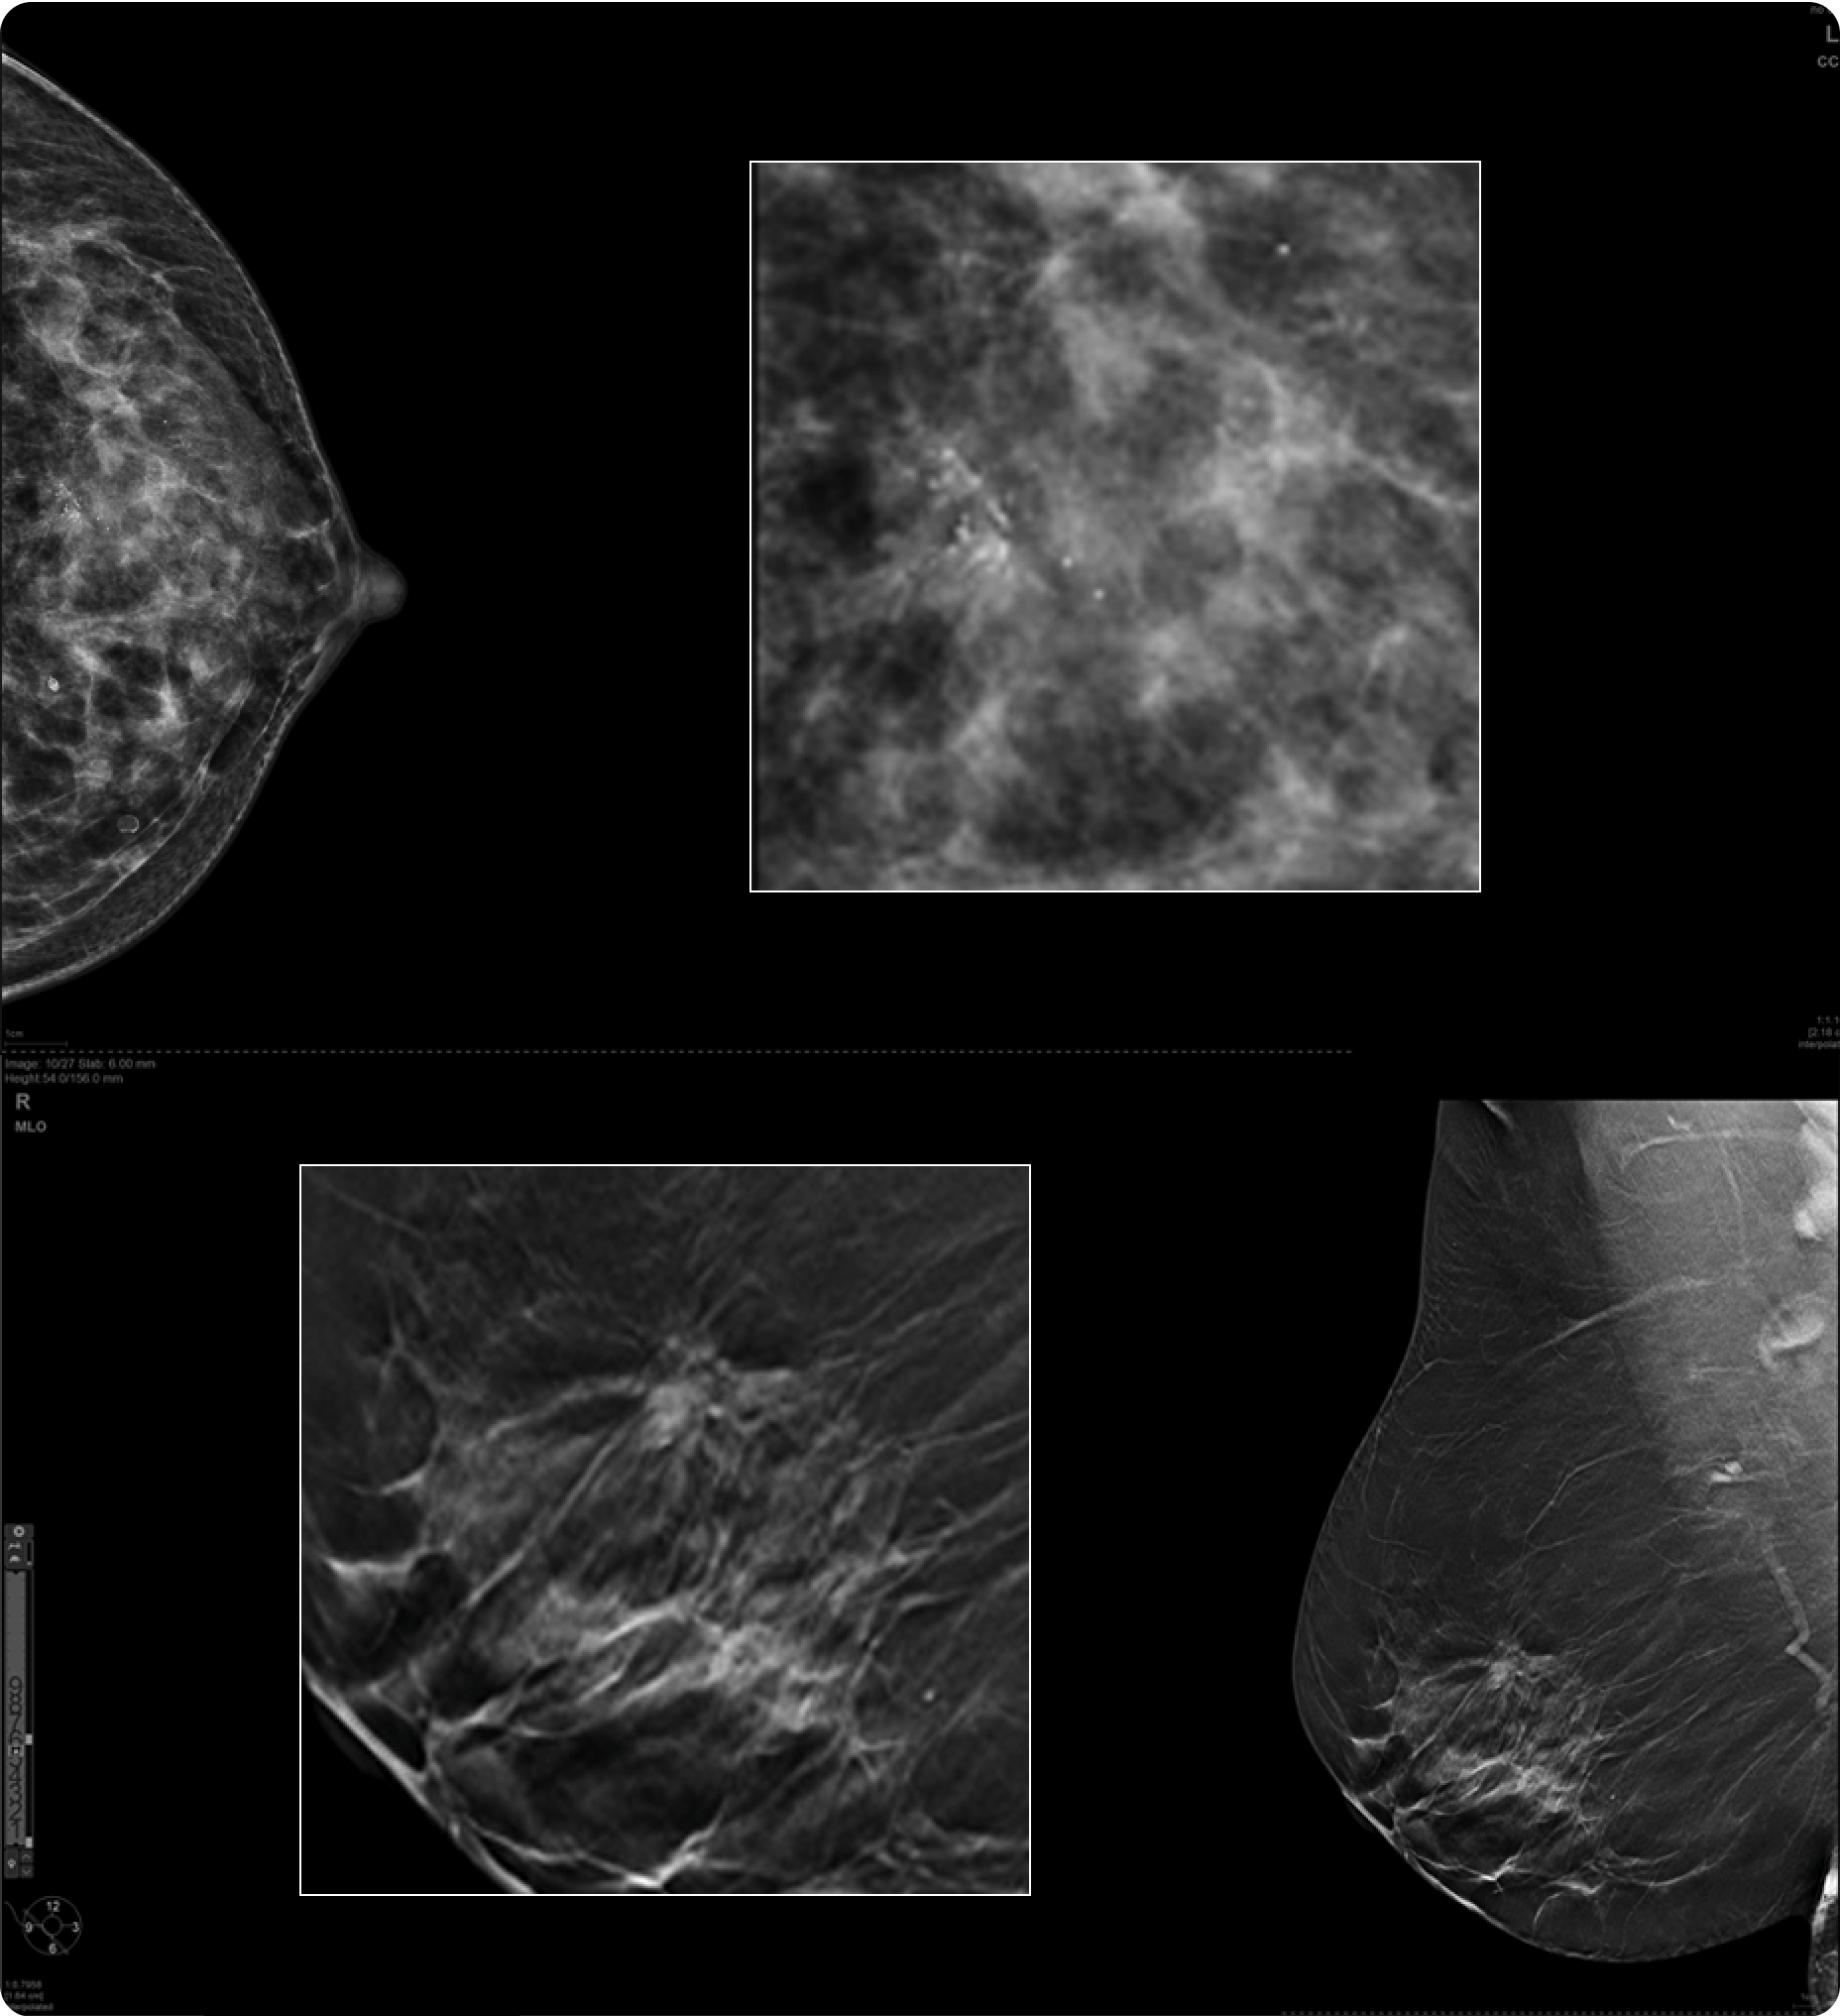

TrueFidelity DL + True Enhance DL

Better together

With the Revolution Ascend Platform, you can combine both of our AI-based imaging reconstruction technologies to create one stunning image. By combining True Enhance DL with TrueFidelity DL, you can achieve images that have less noise, enhanced sharpness and better noise texture than images obtained with ASiR-V.

True Enhance DL

Designed to enhance what matters

True Enhance DL is a deep learning-based processing method intended for contrast enhancement of single energy images. True Enhance DL uses a dedicated Deep Neural Network (DNN) trained to estimate monochromatic, 50 keV GSI images from single-energy X-ray. This technology brings four deep learning models that the user can choose depending on different contrast enhancement phases by clinical tasks.

TrueFidelity DL

Deep learning for a deeper understanding

TrueFidelity™ DL is our state-of-the-art image reconstruction technology that uses a DNN to generate high-definition, low-noise CT images. It produces images with exceptional sharpness, low-contrast image quality performance and your preferred noise texture, at the same dose.¹